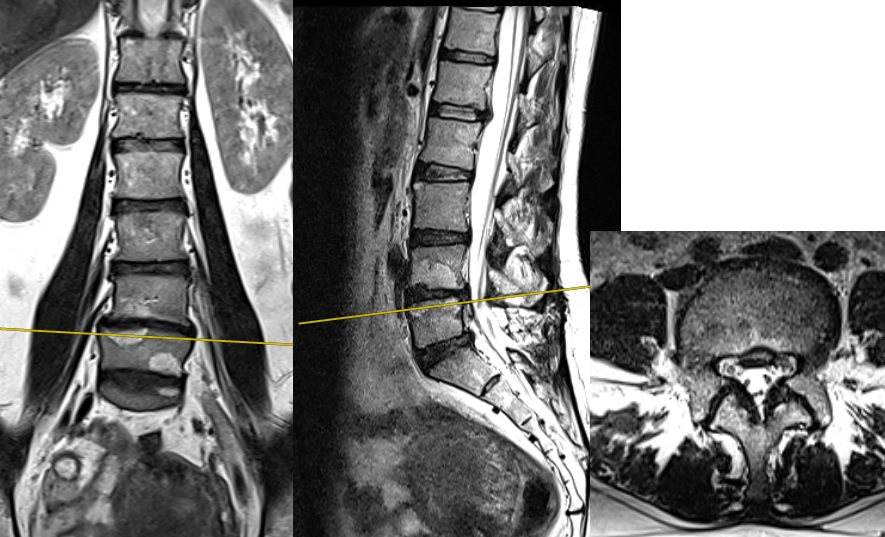

— Вы не могли бы посмотреть МРТ.

— Посмотрел.

— В декабре 2024 г перенесла экстренную операцию на пояснично-крестцовом отделе. Секвестрация грыжи в позвоночный канал, абсолютный стеноз. Парез сгибателей правой стопы.

— Доктор, в приложении снимки поясничного отдела с функциональными пробами на подвижность.

— Посмотрел. Нестабильности нет.